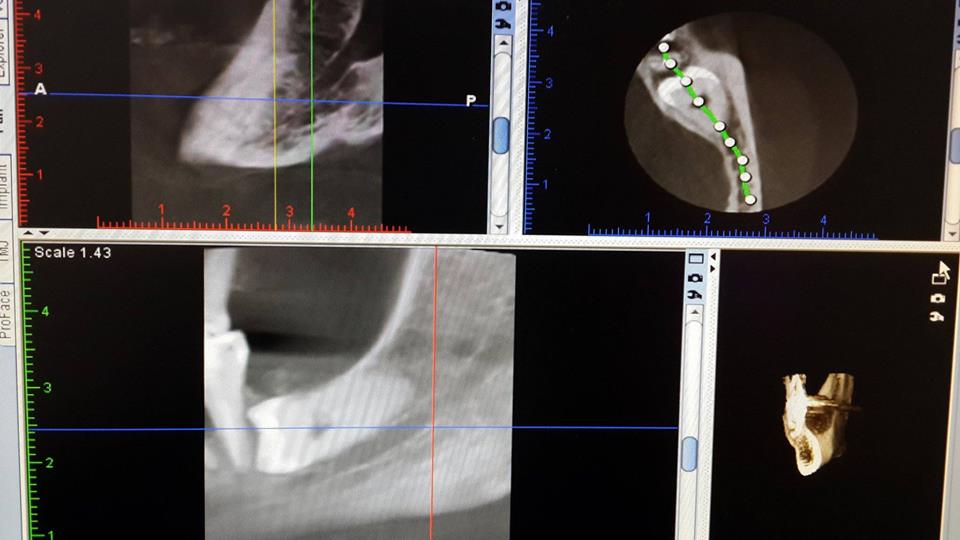

Complex extraction of wisdom tooth

The patient was removed from the retinued tooth of wisdom.